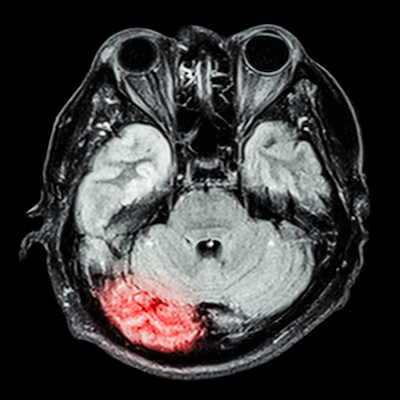

MRI indicates that people in early middle age with poor sleep quality show signs of poor brain health in the form of older brain age later in life, according to research published October 23 in Neurology.

"Sleep problems have been linked in previous research to poor thinking and memory skills later in life, putting people at higher risk for dementia," Cavaillès said. "Our study -- which used brain scans to determine participants' brain age -- suggests that poor sleep is linked to nearly three years of additional brain aging as early as middle age."

Study participants were slotted into three groups: A "low" group with no more than one poor sleep characteristic; a middle group with two or three; and a high group with more than three. At the start of the work, 70% of participants were in the low group, 22% in the middle group, and 8% in the high group. Cavaillès and colleagues assessed participants' brain scans, reviewing the level of brain shrinkage corresponding to age, and used machine learning to determine brain age for each person.

The investigators found that, after adjusting for age, sex, high blood pressure, and diabetes, people in the middle group had an average brain age that was 1.6 years older than those in the low group, and those in the high group had an average brain age that was 2.6 years older. Bad sleep quality, difficulty falling asleep, difficulty staying asleep and early morning awakening were associated with greater brain age, especially when these poor sleep characteristics manifested over a five-year period.